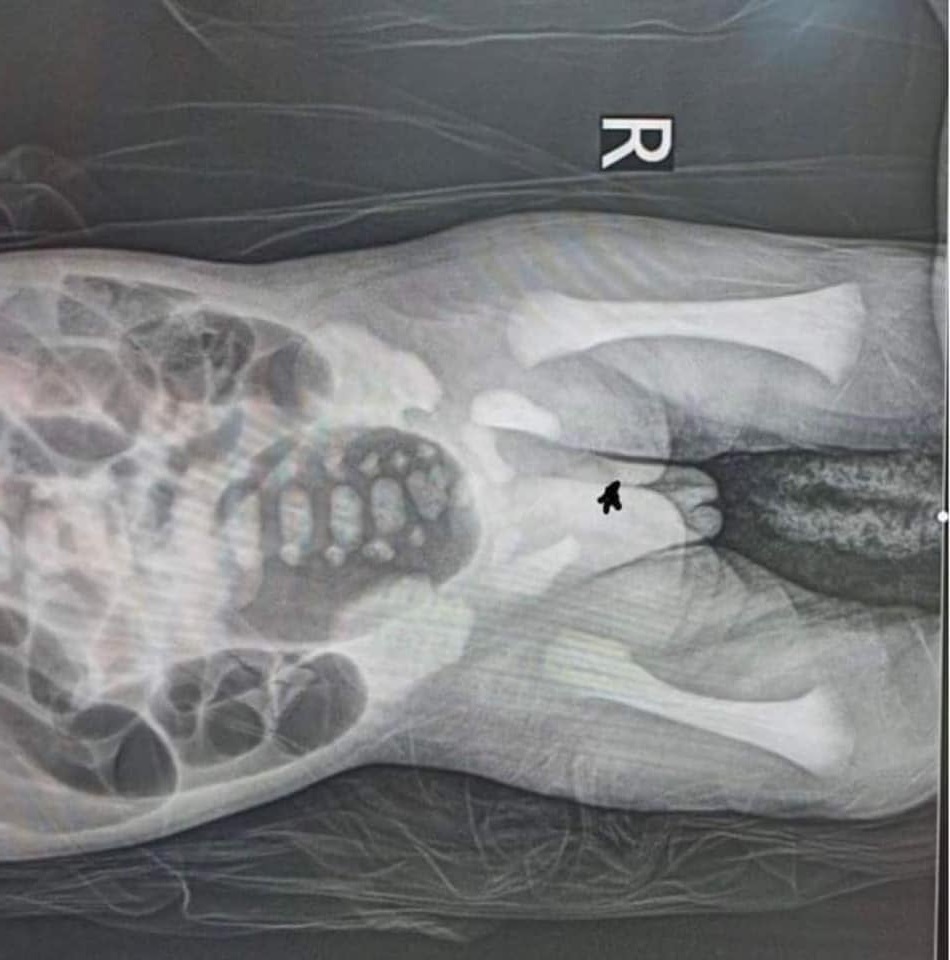

Сэлэнгэ аймгийн Нэгдсэн эмнэлгийн хамт олон төрөлхийн хоол боловсруулах эрхтэн тогтолцооны хөгжлийн гажигтай нярайд эхний шатны яаралтай мэс заслыг амжилттай хийсэн байна.

Мэс заслыг аймгийн Нэгдсэн эмнэлгийн мэс заслын тасгийн эрхлэгч, эмч М.Бямбацогт, мэдээгүйжүүлгийн эмч, Нярайн тасгийн эрхлэгч О.Ганзориг нараар ахлуулсан баг бүрэлдэхүүн телемедицин ашиглан хийсэн бөгөөд ЭХЭМҮТ-ийн хүүхдийн ерөнхий мэс заслын тасгийн эрхлэгч Л.Ганбаяр тэдэнд зөвлөгөө өгсөн аж.